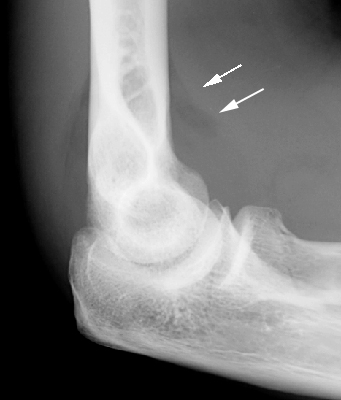

Sail Sign

Elbow effusion

Single lateral radiographs of the elbow which reveals the classic sail sign. This is an invaluable soft tissue finding in cases of intra-articular injury of the elbow. Fat is normally present within the joint capsule of the elbow, but outside the synovium. Typically "hidden" in the concavity of the olecranon and coronoid fossae, the fat is usually not visible on the lateral radiograph. However, injuries that produce intra-articular hemorrhage cause distension of the synovium and forces the fat out of the fossa, producing triangular radiolucent shadows anterior and posterior to the distal end of the humerus. When present in a patient with a history of acute trauma to the elbow, the fat pad sign indicates the presence of an intra-articular hemorrhage, which in turn is often associated with an intra-articular skeletal injury (usually the radial head in an adult).